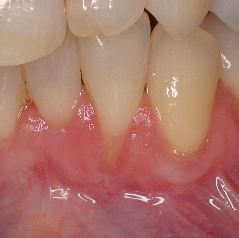

This is a 2 year followup.  This method allows the most esthetic and stable outcomes.